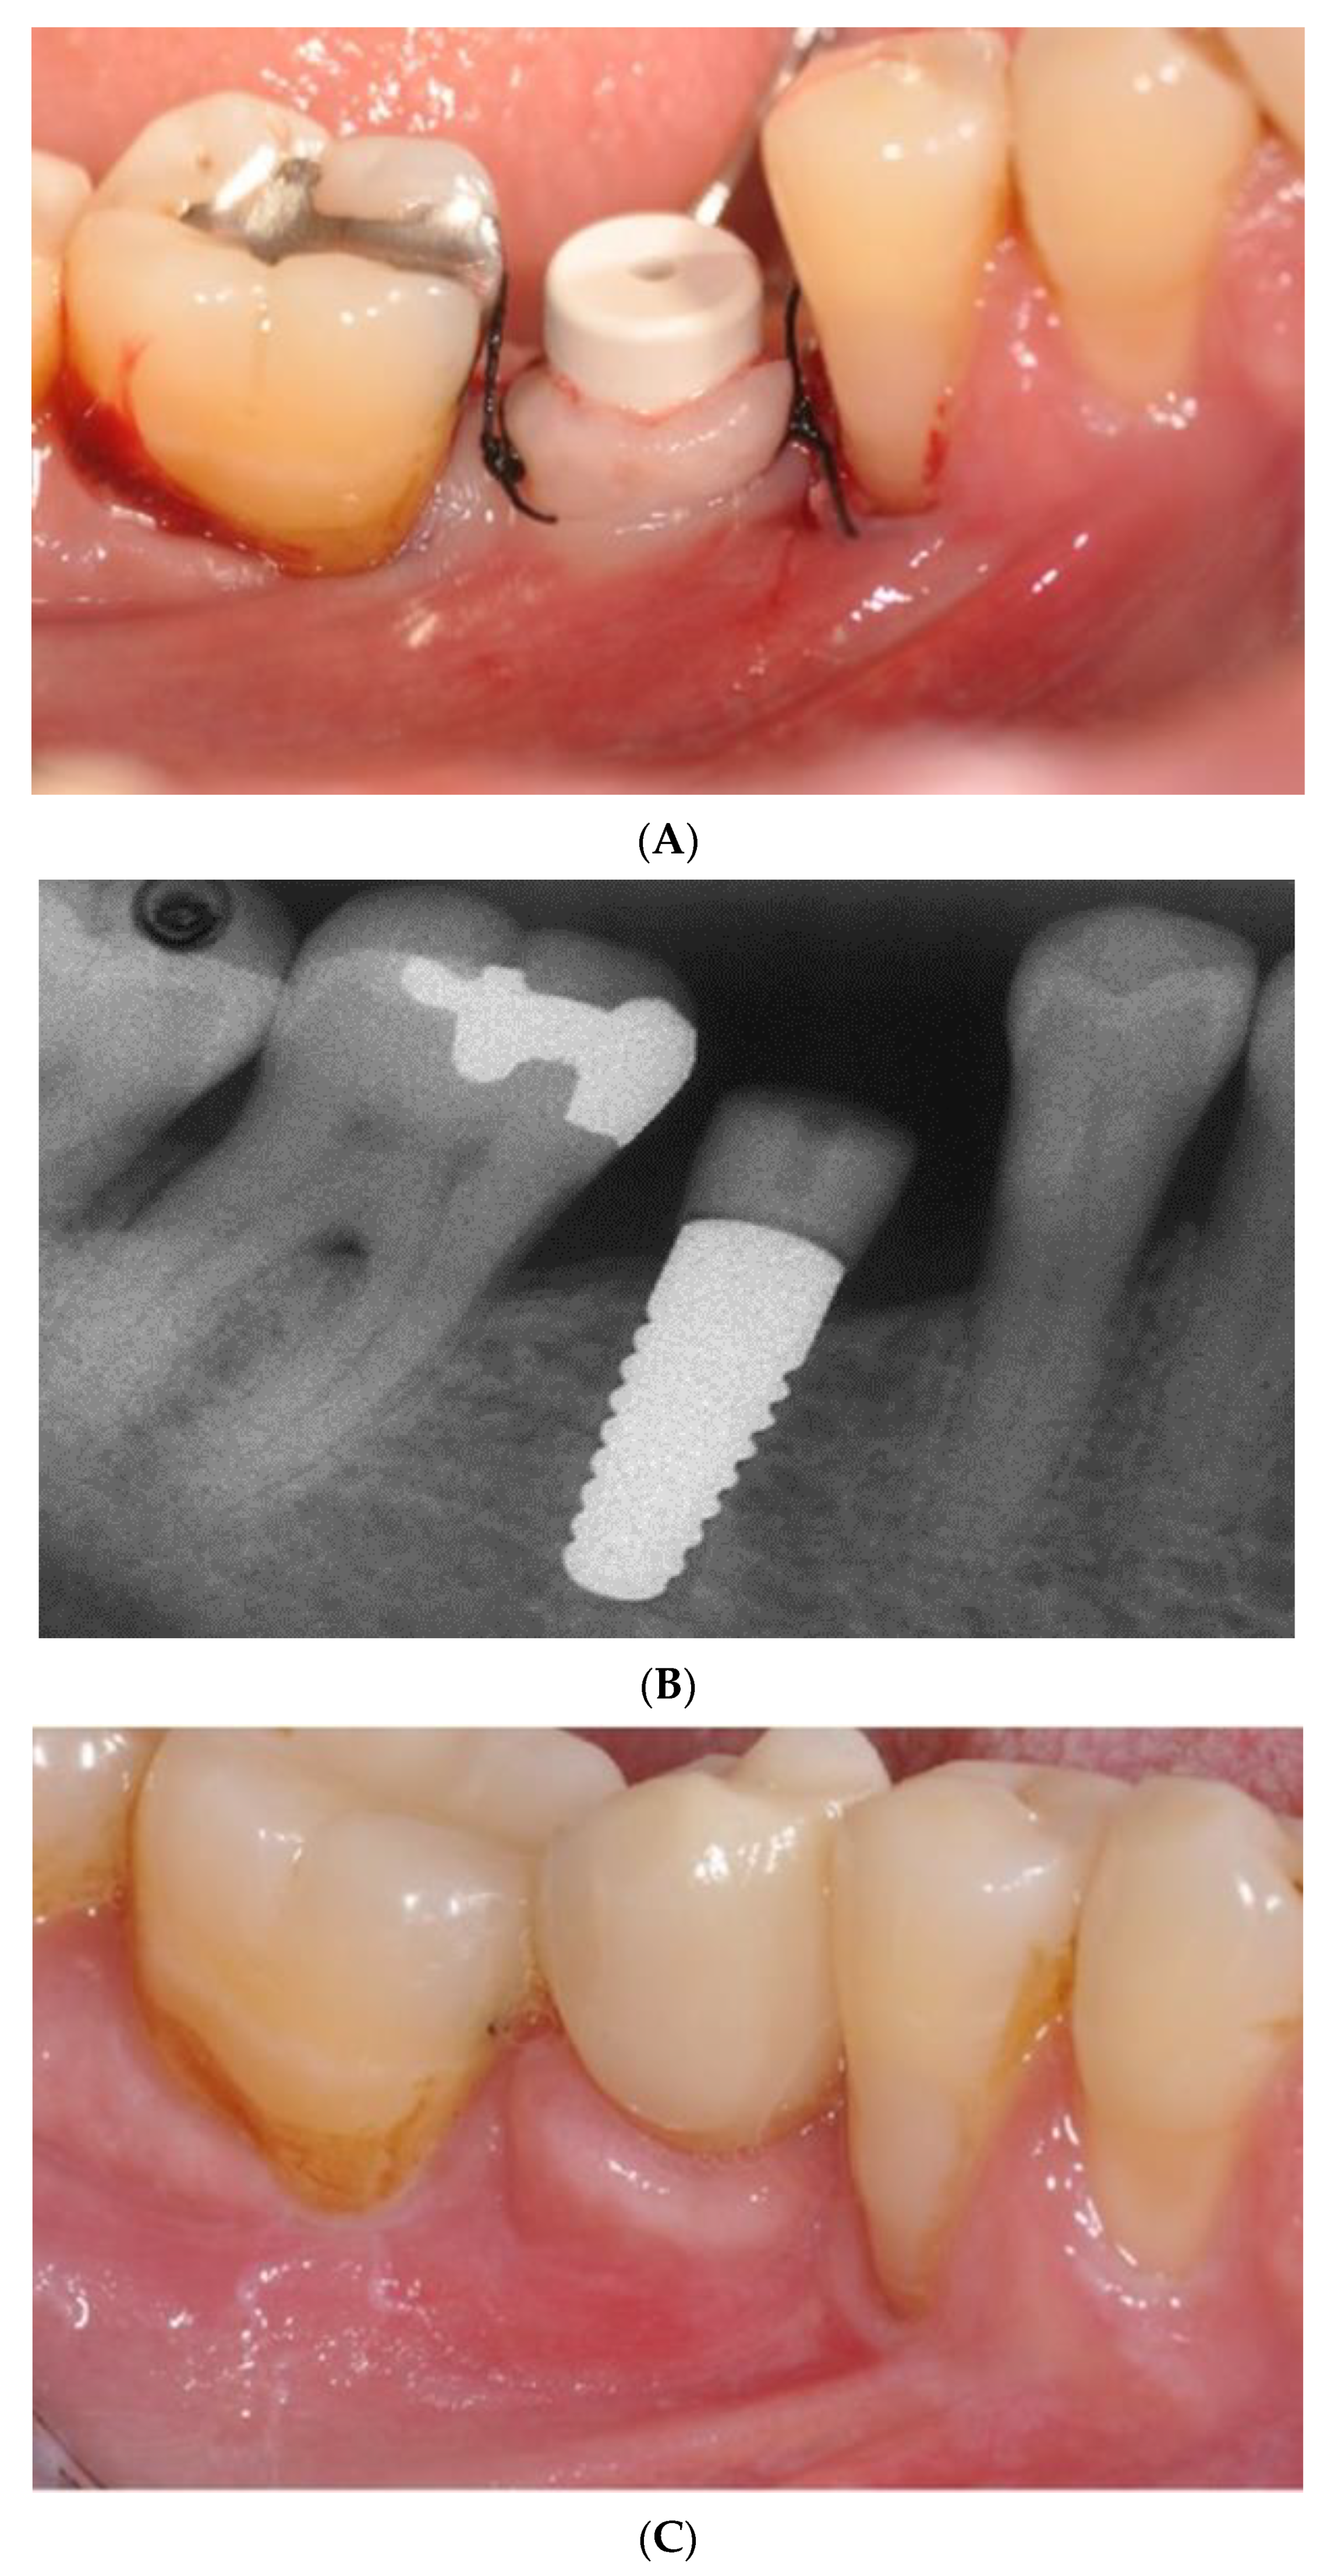

- Pirker, W.; Kocher, A. Immediate, non-submerged, root-analogue zirconia implant in single tooth replacement. Int. J. Oral Maxillofac. Surg. 2008, 37, 293–295. [Google Scholar] [CrossRef]

- Pirker, W.; Kocher, A. Immediate, non-submerged, root-analogue zirconia implants placed into single-rooted extraction sockets: 2-year follow-up of a clinical study. Int. J. Oral Maxillofac. Surg. 2009, 38, 1127–1132. [Google Scholar] [CrossRef]

- Pirker, W.; Wiedemann, D.; Lidauer, A.; Kocher, A.A. Immediate, single stage, truly anatomic zirconia implant in lower molar replacement: A case report with 2.5 years follow-up. Int. J. Oral Maxillofac. Surg. 2011, 40, 212–216. [Google Scholar] [CrossRef]